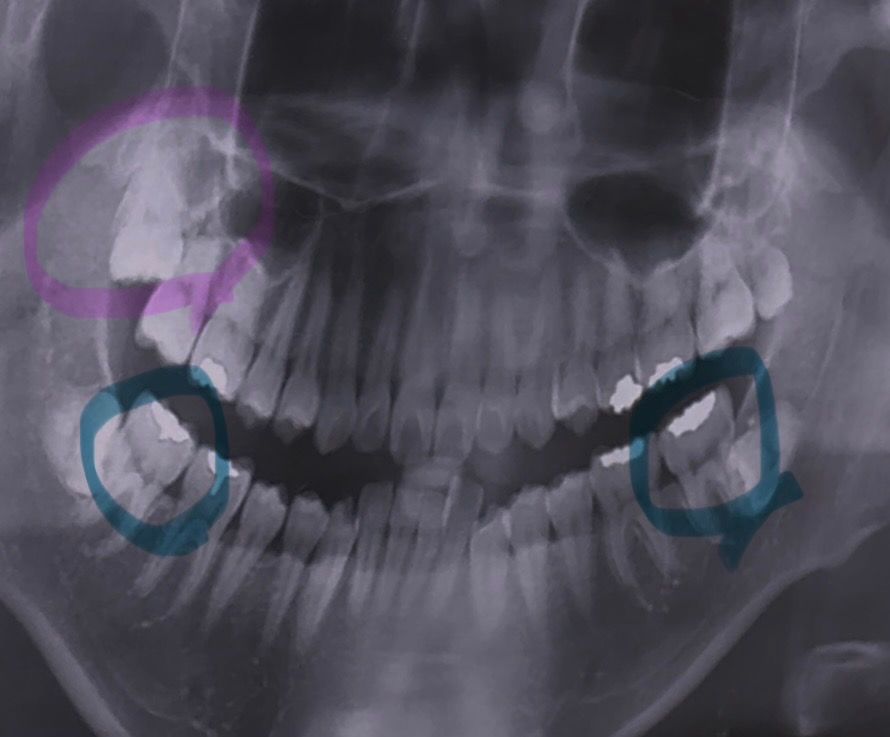

어금니 아래 충치인지 궁금해요(엑스레이)

1. 아래 맨끝에 표시한 어금니 충치인지 봐주세요..

2. 그리고 위에 표시한 사랑니 저거 뺄수있을까요?

너무 위라 빼기에 위험한가요?

1. 충치로 보여지진 않습니다만 충치가 생길 위험이 크긴 하네요

2. 위 사랑니 뺄 수 있습니다 일반 사랑니보단 난이도가 높을 수 있습니다

방사선사진으로는 충치의 여부를 정확하게 파악하기 어려워 보입니다. 상악의 사랑니는 깊게 매복되어 있으며 특별한 문제를 발생시키지 않기때문에 굳이 발치를 할필요는 없을것으로 생각됩니다.

자세한 확인을 위해서 치과에서 진료를 받아보는 것을 권유드립니다.